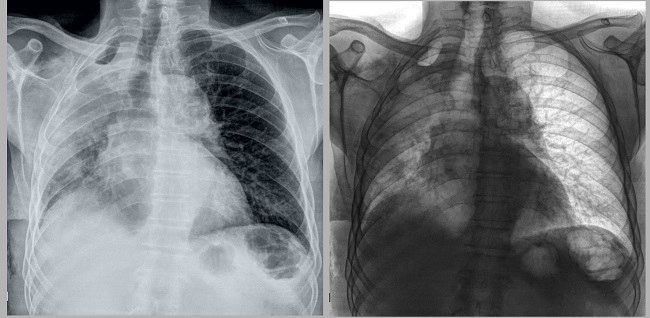

Pengecilan Paru Paru

7 Penyebab Paru Paru Mengecil Sebelah Yang Mematikan Halosehat

Pneumothorax Spontan Mymandapanda S Persib Blog

5 Obat Paru Paru Kempes Sebelah Di Apotik By Irwan Muhammad Linkedin

Atelektasis Gejala Penyebab Dan Mengobati Alodokter